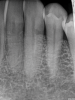

(7.) Radiographic presentation of ECR in tooth No. 22. Note the distal-cervical portal of entry and how the shape of the root canal is visibly distinct from the resorptive lesion.

Figure 7

When using periapical radiographs in diagnosis, external resorptive defects should appear to move when captured from differing angulations and will have a visible and intact pulp chamber in all but advanced cases.1 All radiographic findings can help to differentiate ECR lesions from internal root resorption lesions, which have symmetrical, smooth, and clearly defined walls that appear to balloon out from the pulp chamber and do not appear to move with multiple parallax images. Conversely, ECR lesions have a less defined, irregular, and "ragged" or "moth-eaten" appearance and demonstrate variations in density, which makes them distinct from internal root resorption lesions that are usually uniform in density (Figure 7).2,14

On radiographs, early ECR lesions may exhibit a diminutive spot at the cementoenamel junction (CEJ), which may be confused with cervical burnout, but throughout the majority of the lesion, the root canal should be visible and intact. Advanced ECR lesions will appear as large radiolucent areas with less well-defined or "moth-eaten" borders that can extend into the pulp space.25 If an ECR lesion is in the repair-remodeling stage of development, it may appear more radiopaque due to the ossification of granulation tissue. Radiopaque spots may also be observed due to disruption of the PRRS that has led to local calcification of pulp tissue.6